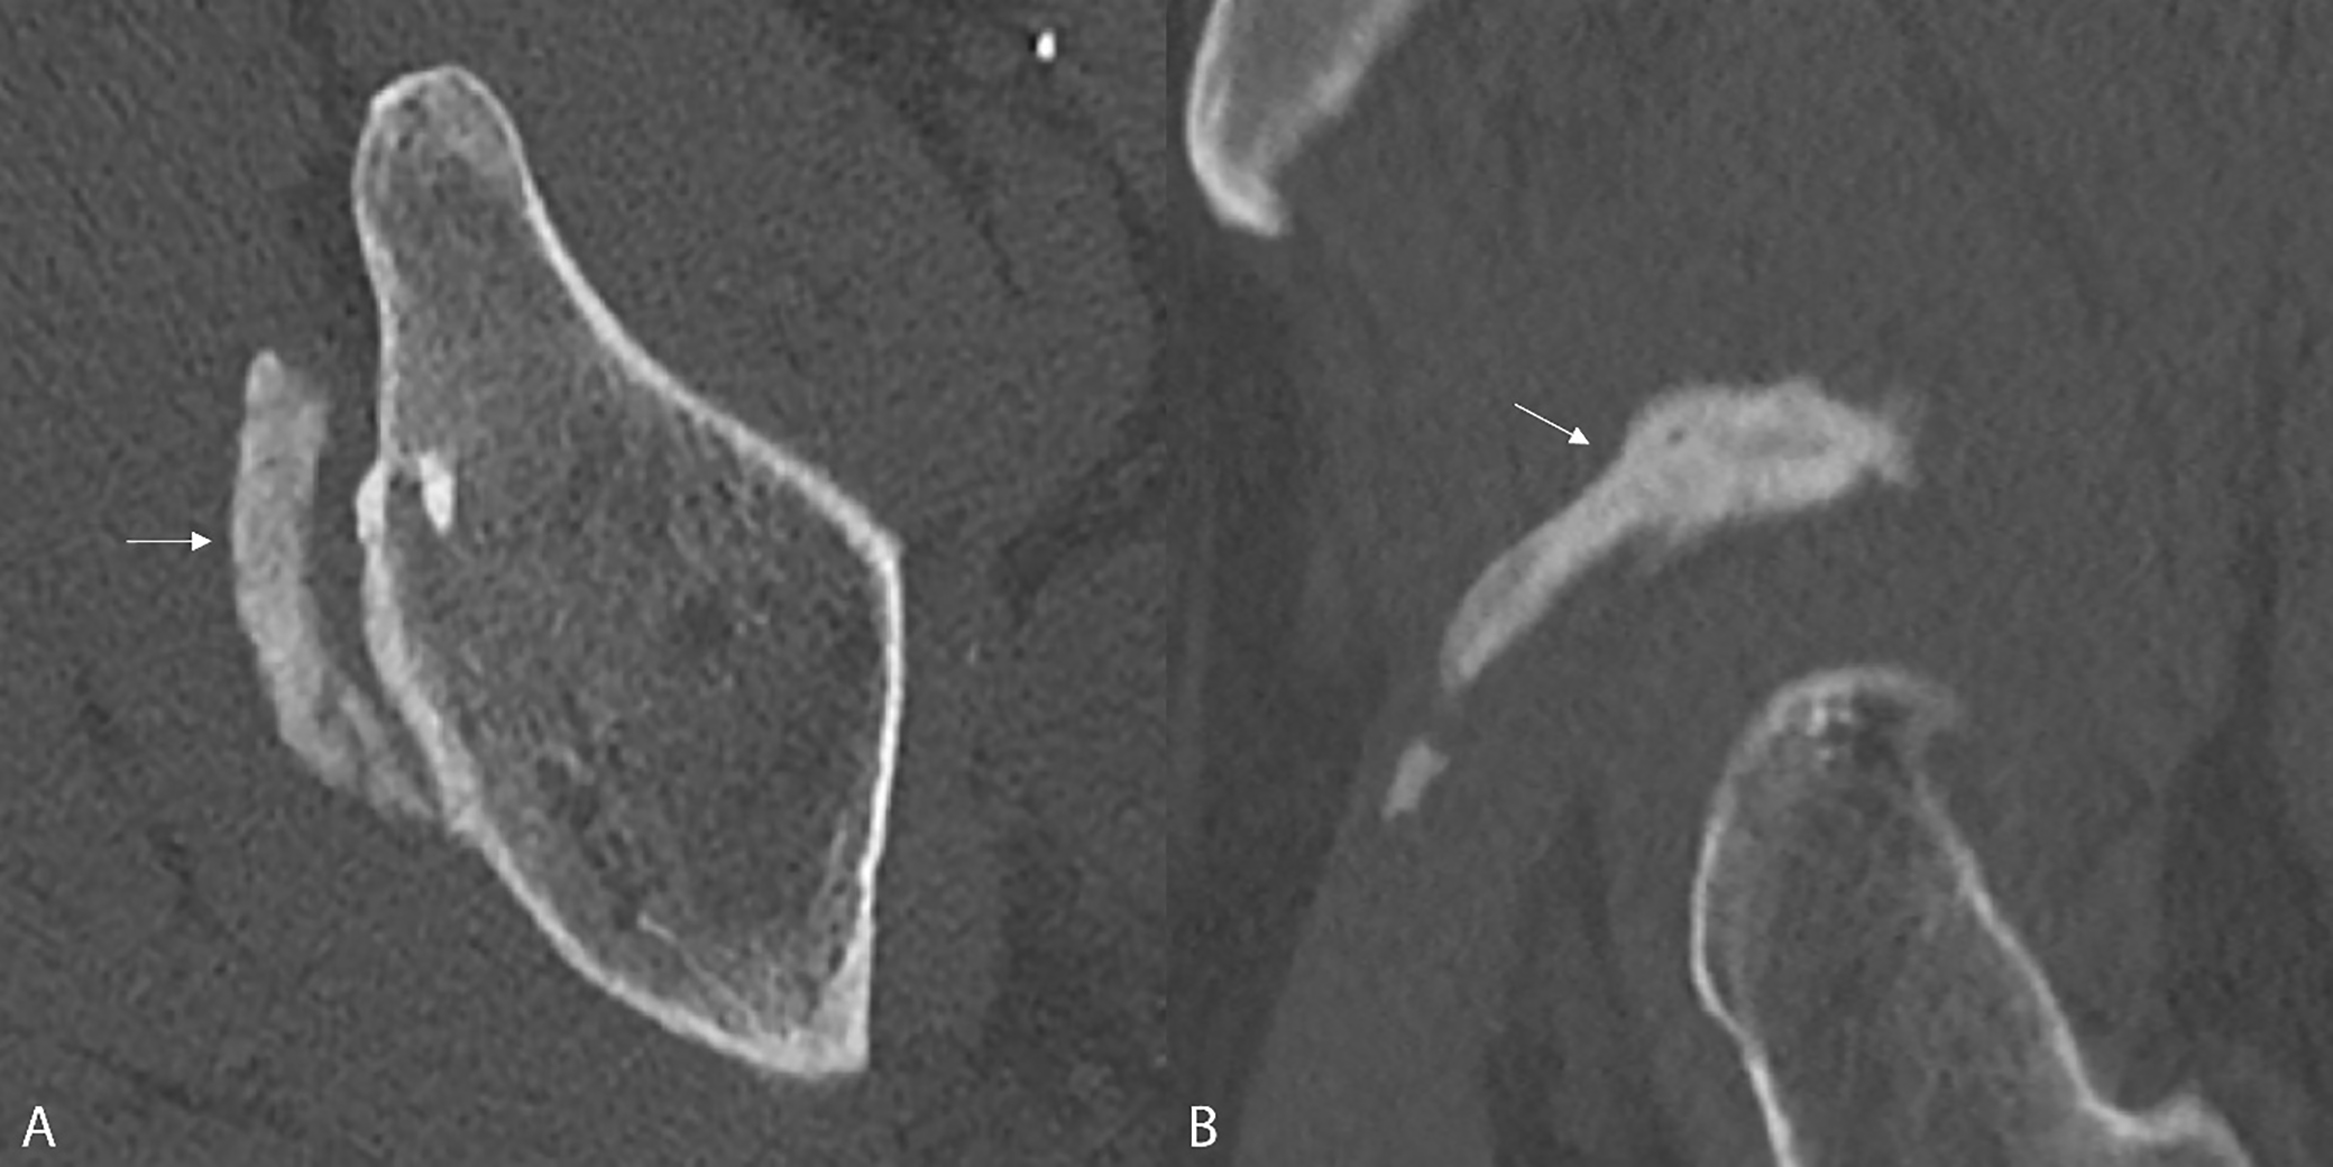

Figure 3 A‑B.

Computed Tomography confirms HO with elongated morphology superior to the acetabular rim (arrows).